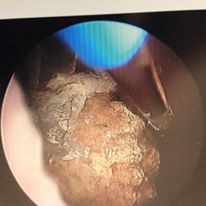

Got stones? What to do with them in the kidney but they aren’t blocking- a very common question.

Your Best Management for Asymptomatic Nonobstructing Kidney StonesUrology – August 30, 2015 – Vol. 33 – No. 2 Lower-pole kidney stones are less likely to become symptomatic during observation.

A stone in your kidney but no pain…what to do?

In general “if it ain’t broke don’t fix it” however…read on…

Your Best Management for Asymptomatic Nonobstructing Kidney Stones